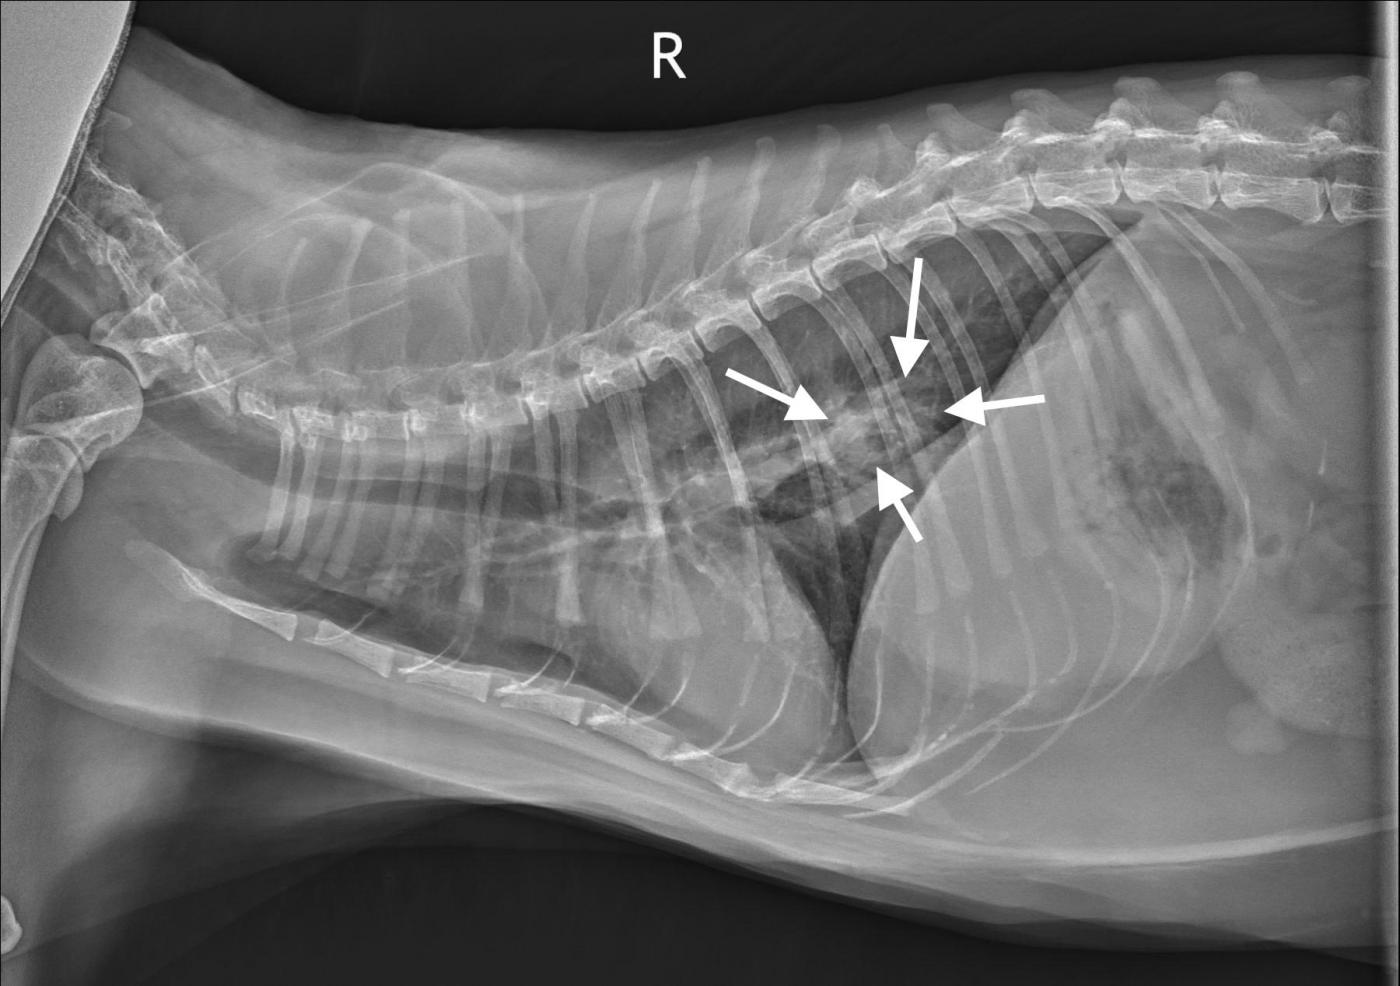

Lung Digit Syndrome Dog. Usually, this tumour forms a single, large mass in the lung. Pulmonary metastases (also known as “lung metastases” or “lung mets”) can be asymptomatic early on.

This results from metastasis from the pulmonary carcinoma to the toes (digits), causing swelling, pain, and lameness. Pulmonary metastases (also known as “lung metastases” or “lung mets”) can be asymptomatic early on. Soft tissue swelling surrounds p2 and p3 of the third digit, representing a metastatic neoplasm.

Usually, this tumour forms a single, large mass in the lung. Primary lung tumors in dogs may occur as single or multiple circumscribed mass lesions, as a diffuse lung pattern, or as a lobar consolidation. Primary lung tumors have variable signs, which depend on the location of the tumor, rate of tumor growth, and the presence of previous or current lung disease.

In cats, single circumscribed mass lesions are. This results from metastasis from the pulmonary carcinoma to the toes (digits), causing swelling, pain, and lameness. The most common signs in dogs include coughing, weight loss, lethargy, and.

The lung is the most common location for metastatic osteosarcoma. On the one hand, this most likely results from the angioinvasive. Cats with primary lung tumors can have metastases to the digits, so thorough exam and radiographs of all feet should be considered if a lung tumor is found in a cat.